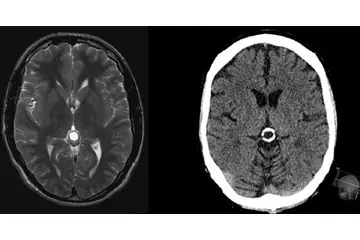

Bebeklerde beyin kistleri, genellikle doğumdan önce veya doğum sırasında oluşabilen sıvı dolu keseciklerdir. Bu kistler, beyin dokusunda veya çevresinde yer alabilir ve çoğu zaman zararsızdır. Ancak bazı durumlarda, beyin kistleri beyin fonksiyonlarını etkileyebilir ve tedavi gerektirebilir. Bu makalede, bebeklerde beyin kistlerinin belirtileri, tanısı ve tedavi yöntemleri hakkında detaylı bilgi verilecektir. Bebeklerde Beyinde Kist Belirtileri Bebeklerde beyin kistlerinin belirtileri genellikle kistin boyutuna, konumuna ve etkilerine bağlıdır. Belirtiler şunları içerebilir:

Bu belirtiler, kistin beyin üzerindeki etkilerine bağlı olarak değişiklik gösterebilir. Dolayısıyla, ebeveynlerin bebeklerinde bu tür belirtiler gözlemlemesi durumunda hızlı bir tıbbi yardım alması önemlidir. Bebeklerde Beyin Kistlerinin Tanısı Bebeklerde beyin kistlerinin tanısı genellikle aşağıdaki yöntemlerle yapılır:

Bu tanı süreçleri, doktorun kistin doğasını anlamasına ve uygun tedavi yöntemini belirlemesine yardımcı olur. Bebeklerde Beyin Kistlerinin Tedavisi Bebeklerde beyin kistlerinin tedavisi, kistin türüne, boyutuna ve bebeğin genel sağlık durumuna bağlı olarak değişiklik göstermektedir. Tedavi seçenekleri şunlardır:

Hocam kusura bakmayin özür dilerim eşim 6 aylık hamile ve çocuğumuzun kafasında anekoik kistik lezyon görüldü tek birtane ve 18 16 mm çapın da ilerleyen zamanlarda bi sıkıntı olurmu

Merhaba, öncelikle eşinize ve size sağlık diliyorum. Bu tür kistik lezyonlar bazen bebeklerde görülebilir ve çoğu zaman kendiliğinden kaybolabilir. Ancak, doğru bilgi ve takip için mutlaka bir perinatoloji uzmanına veya kadın doğum uzmanına danışmanızda fayda var. Hepsinin ötesinde doktorunuzun önerilerini dikkate almanız en doğru adım olacaktır. Geçmiş olsun.